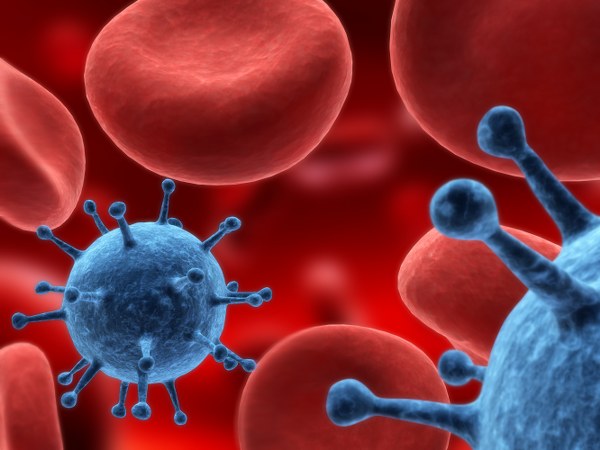

Почти пять тысяч человек заинтересовались первой частью и второй частью профессионального клипарта на тему человеческих мышц и органов, поэтому я спешу представить вам третью часть замечательного клипарта. Анатомия - раздел биологии и конкретно морфологии, изучающий строение тела организмов и их частей на уровне выше клеточного. Предлагаю скачать высококачественный растровый клипарт на тему анатомии человека, его мышц и органов. С помощью этого клипарта можно изучить практически все мышцы человека, узнать структуру и строение или просто применить эти фотографии для необходимых вам рекламных материалов, буклетов, разделов о спорте и спортивном питании. Если вы занимаетесь профессиональным спортом, то данный клипарт будет вам полезен и интересен. Архив содержит различные материалы, включая картинки и фото низкого разрешения, не касающиеся непосредственно анатомии, но это не делает клипарт хуже, а напротив - дает массу возможностей для ваших творческих нужд.